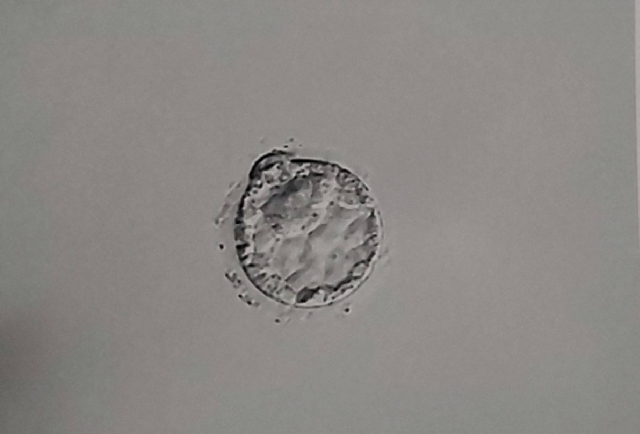

体外受精(IVF)で胚盤胞凍結をされた方が、治療をやめるに際し胚盤胞の供養をして欲しいと実際に御供養に来院されるケースが近年増えてきています。

不妊治療は「出口の見えないトンネル」とも言われ、頑張って治療と向き合って来た自身の区切りとして、そして胚盤胞であってもかけがえのない我が子への想いを込めて御供養をされる方がいらっしゃいます。